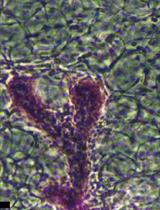

Check the BMP files to ensure they correctly represent the amount of bone visualized. You will notice that the images for the lowest threshold will include much non-bone material. This lowest threshold will not be used for analysis of your samples (Figure 3B).

Figure 3. An example of the four thresholds applied to a femoral region of interest. A. Screenshot of the 4 levels derived from the automated Otsu thresholding method from a single sample. B. BMP file showing the four levels applied to a slice through the femur. C. A histogram of pixel intensities for a metaphyseal region of interest with arrows to show the Otsu levels defined in panel A, showing which level is discarded, and the calibrated density values that correspond to those levels. D. A pseudo-color image of panel B showing the three bone density levels measured.